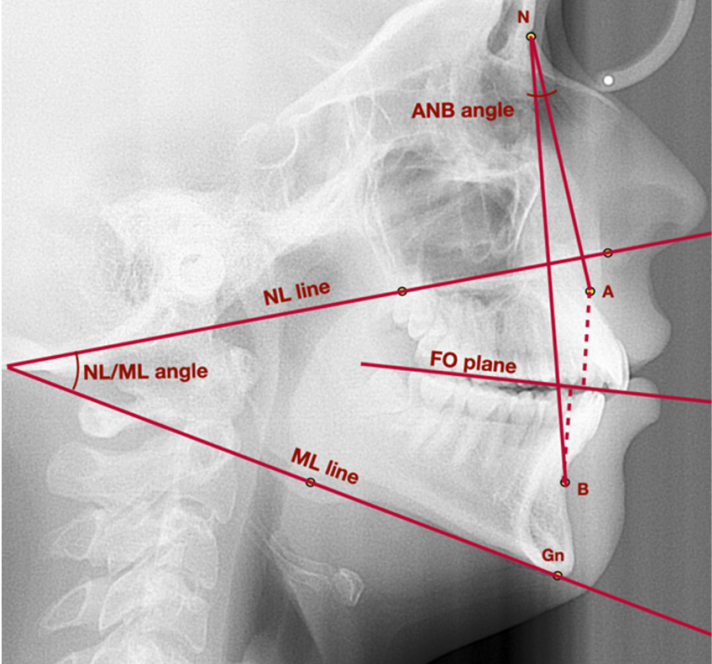

Dentofacial Orthopedics and Maxillary Morphogenesis

Tuesday, 16 September 2025